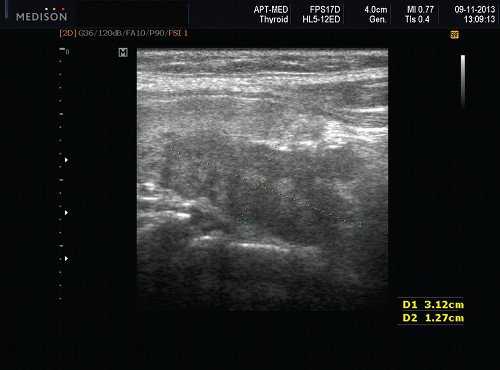

Сиаладениты - большая группа полиэтиологических воспалительных заболеваний СЖ (рис. 3). Первичные сиаладениты - сиаладениты, рассматриваемые в качестве самостоятельных заболеваний (например, эпидемический паротит). Вторичные сиаладениты - сиаладениты, являющиеся осложнениями или проявлениями других заболеваний (например, сиаладенит при гриппе). Эхографическая картина при разной этиологии малоспецифична. Этиология имеет клиническое значение в процессе определения тактики лечения.

Рис. 3. Сиаладенит правой поднижнечелюстной слюнной железы.

Рис. 4. Постлучевой сиаладенит.